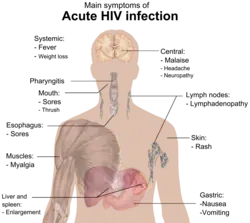

The stages of HIV infection are acute infection (also known as primary infection), latency, and AIDS. Acute infection lasts for several weeks and may include symptoms such as fever, swollen lymph nodes, inflammation of the throat, rash, muscle pain, malaise, and mouth and esophageal sores. The latency stage involves few or no symptoms and can last anywhere from two weeks to twenty years or more, depending on the individual. AIDS, the final stage of HIV infection, is defined by low CD4+ T cell counts (fewer than 200 per μL), various opportunistic infections, cancers, and other conditions.

Acute HIV infection, primary HIV infection or acute seroconversion syndrome[1]: 416 is the first stage of HIV infection. It occurs after the incubation stage, before the latency stage, and the potential AIDS succeeding the latency stage.

During this period (usually days to weeks post-exposure) fifty to ninety percent of infected individuals develop an influenza or mononucleosis-like illness called acute HIV infection (or HIV prodrome),[2][3] the most common symptoms of which may include fever, lymphadenopathy, pharyngitis, rash, myalgia, malaise, mouth and esophageal sores, and may also include, but less commonly, headache, nausea and vomiting, fatigue, ulcers in the mouth or on the genitals, enlarged liver/spleen, weight loss, thrush, night sweats and diarrhea and neurological symptoms. Infected individuals may experience all, some, or none of these symptoms.[4] The duration of symptoms varies, averaging 28 days and usually lasting at least a week.[5]

Because of the nonspecific nature of these symptoms, they are often not recognized as signs of HIV infection. Even if patients go to their doctors or a hospital, they will often be misdiagnosed as having one of the more common infectious diseases with the same symptoms. As a consequence, these primary symptoms are not used to diagnose HIV infection, as they do not develop in all cases and because many are caused by other more common diseases. However, recognizing the syndrome can be important because the patient is much more infectious during this period.[6]